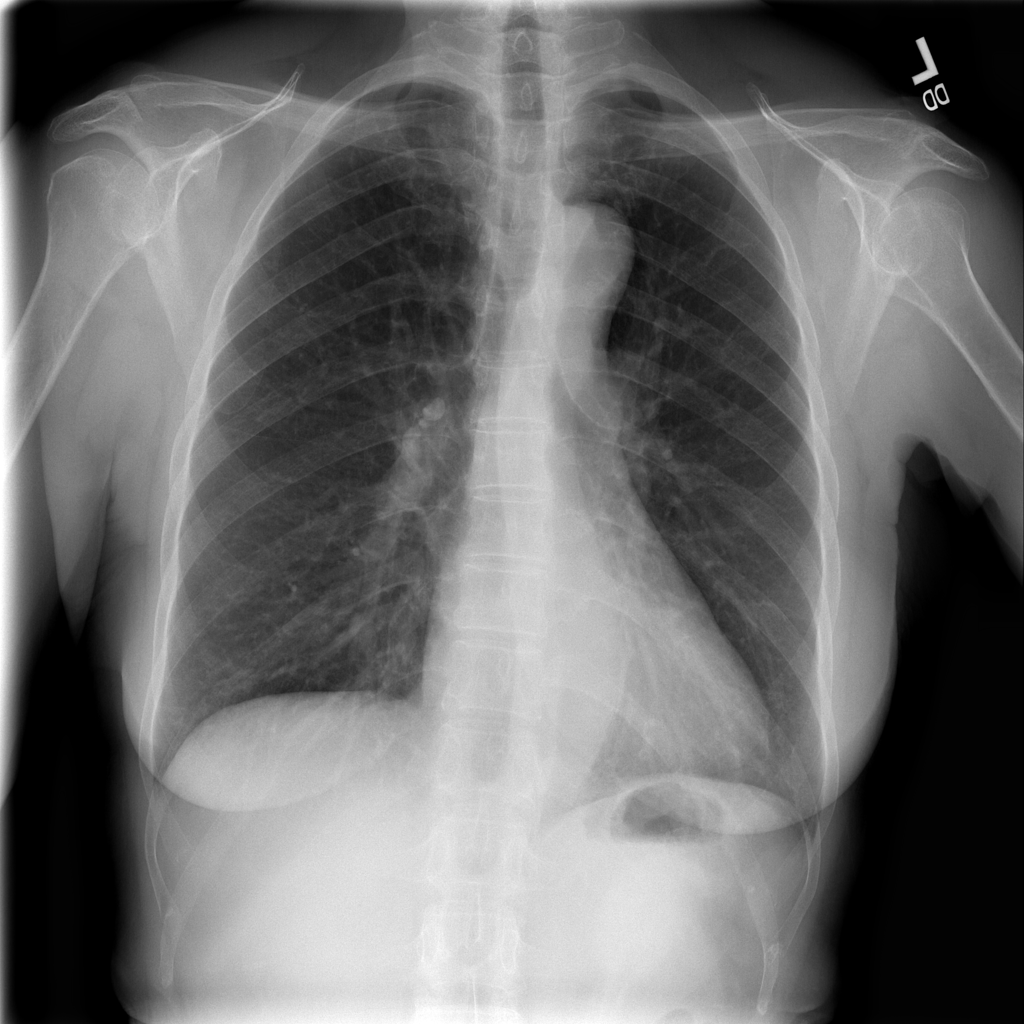

Showing up to 90 reference images for Nodule.

PAT-250B · IMG-000Nodule

PAT-250B · IMG-000

PA